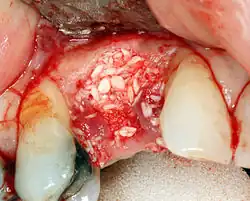

Additional procedures to augment deficient bone in implant site

For an implant to osseointegrate, it needs to be surrounded by a healthy quantity of bone. In order for it to survive long-term, it needs to have a thick healthy soft tissue (gingiva) envelope around it. It is common for either the bone or soft tissue to be so deficient that the surgeon needs to reconstruct it either before or during implant placement.[50]: 1084 All techniques of augmenting the alveolar bone in preparation for implant placement are invasive and associated with a degree of morbidity.[59]

Hard tissue (bone) reconstruction

Bone grafting is necessary when there is a lack of bone. It also helps to stabilize the implant by increasing survival rates of the implant and decreasing marginal bone level loss.[60] While there are always new implant types, such as short implants, and techniques to allow compromise, a general treatment goal is to have a minimum of 10 mm (0.39 in) in bone height, and 6 mm (0.24 in) in width. Alternatively, bone defects are graded from A to D (A=10+ mm of bone, B=7–9 mm, C=4–6 mm and D=0–3 mm) where an implant's likelihood of osseointegrating is related to the grade of bone.[61]: 250

To achieve an adequate width and height of bone, various bone grafting techniques have been developed. The most frequently used is called guided bone graft augmentation where a defect is filled with either natural (harvested or autograft) bone or allograft (donor bone or synthetic bone substitute), covered with a semi-permeable membrane and allowed to heal. During the healing phase, natural bone replaces the graft, forming a new bony base for the implant.[56]: 223

Three common procedures are:[61]: 236

- Sinus lift

- Lateral alveolar augmentation (increase in the width of a site)

- Vertical alveolar augmentation (increase in the height of a site)